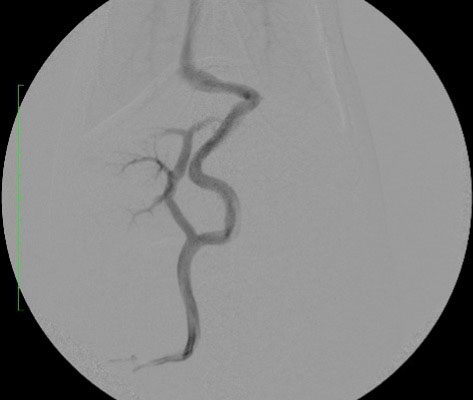

手術紹介

門脈体循環シャント